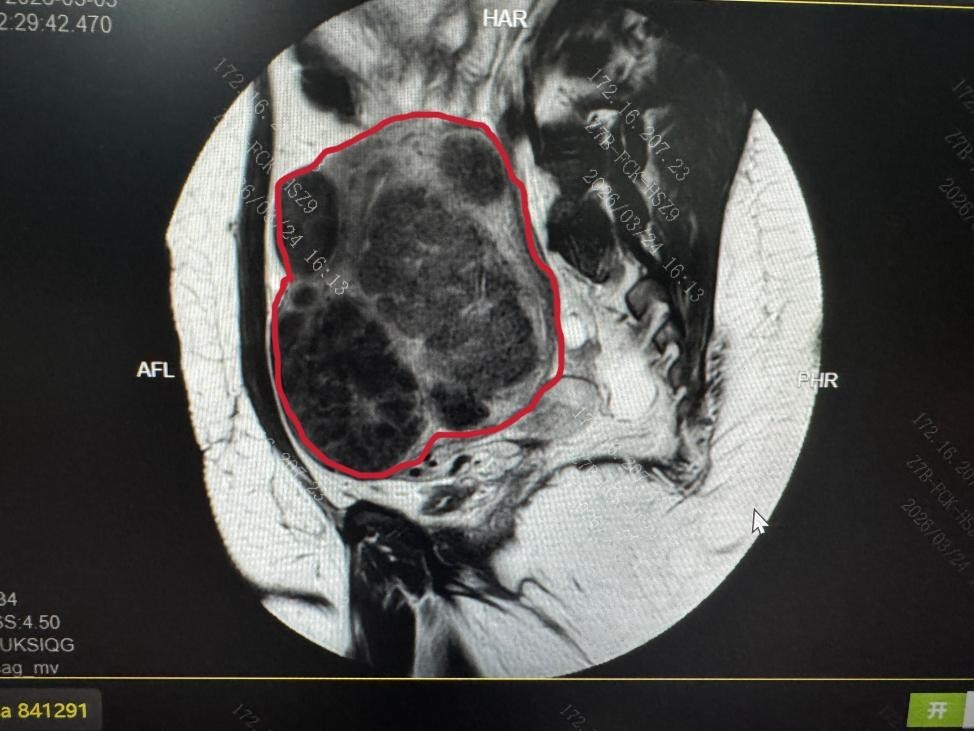

PUSH术前患者MRI子宫图像(红色线内区域为子宫)及子宫内弥漫存在的肌瘤影

弥漫性子宫肌瘤病是一种特殊类型的子宫肌瘤,临床以月经过多、继发性贫血、不孕为主要表现,其早期症状与普通痛经、月经不调高度相似,极易被患者忽视,多数患者子宫内肌瘤呈弥漫性生长,临床治疗棘手。

与有完整包膜、边界清晰的普通多发性子宫肌瘤不同,弥漫性子宫肌瘤病的肌瘤常无完整包膜,像沙粒一样弥漫性浸润整个子宫肌层,大大小小的瘤体与正常肌层交织在一起,肉眼难以分辨清晰边界,给手术治疗带来极大挑战。